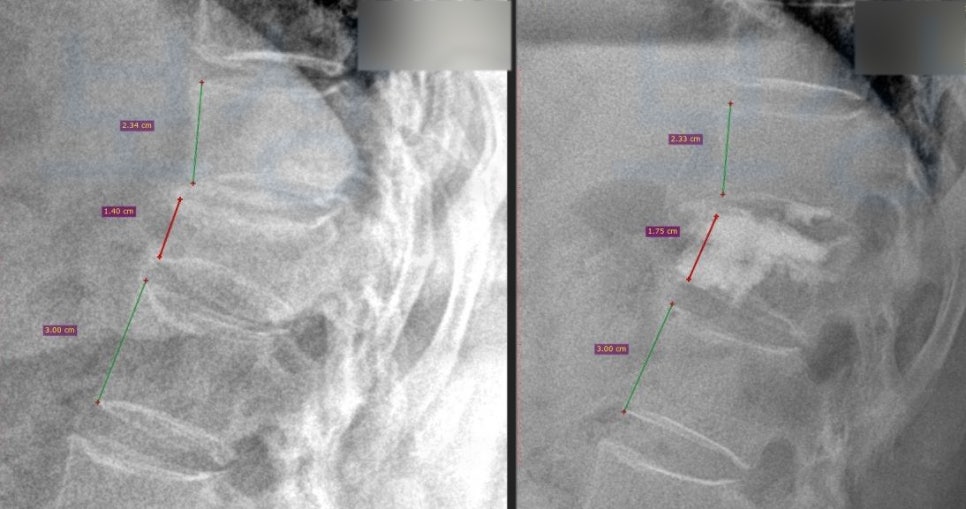

의뢰인은 환경 미화원으로 일하시면서 바닥을 물걸레질 하시다 미끄러져 넘어지는 사고를 당하셨습니다. 그런데 이 사고로 의뢰인은 허리에 극심한 통증을 호소하셨고 병원에 내원하여 정밀검사를 받아보니 흉추12번 압박골절 진단을 받으셨죠.